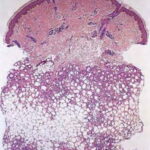

Histopathology. Focal areas of fat necrosis are present in the fat lobules and are infiltrated by macrophages and foreign body-type giant cells (Fig. 20-28). Fat deposits in the macrophages and giant cells contain crystalline fat, which after lipid extraction appears as needle-shaped clefts in a radial arrangement . In frozen sections, the radial clefts contain doubly refractile crystals. Calcium deposits usually are small and scattered in the necrotic fat. If the necrosis is |

extensive, calcium deposits may be large and require several years to be reabsorbed. |